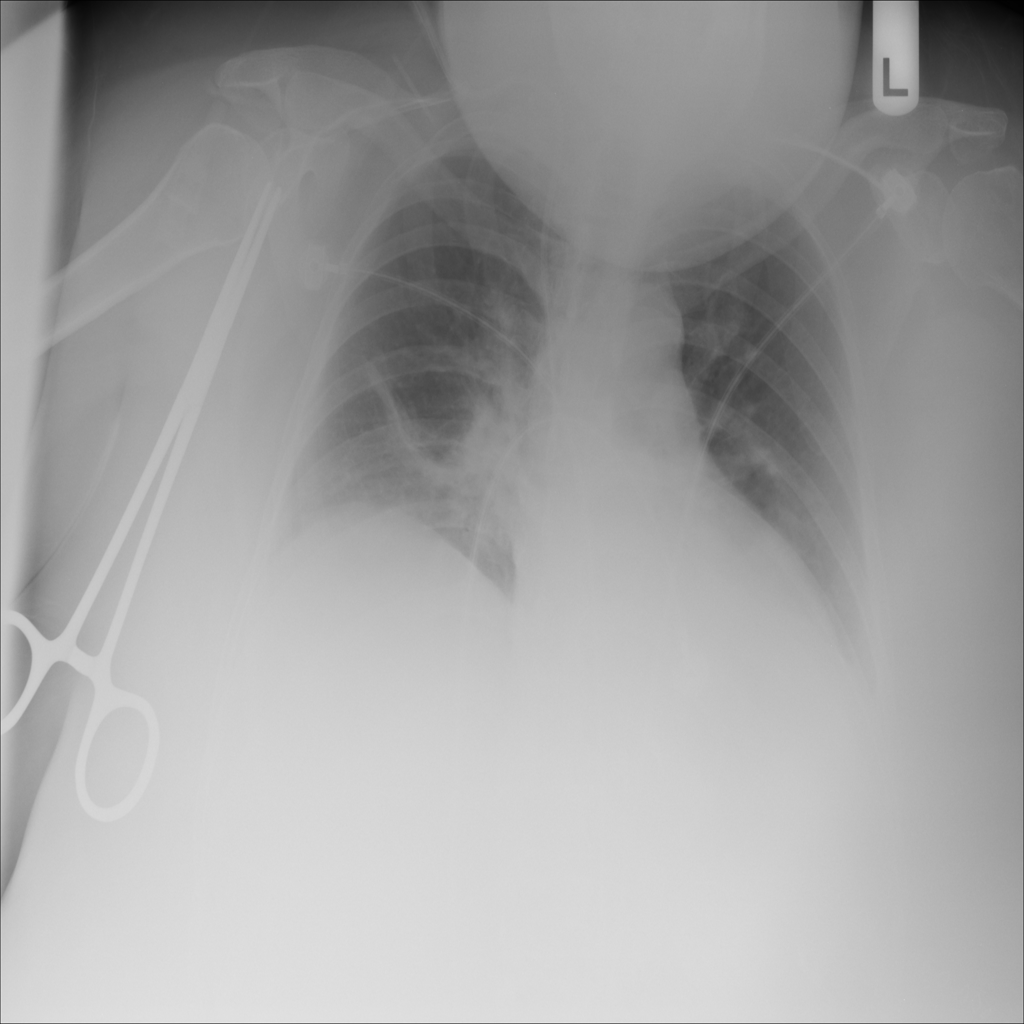

PAT-86C8 · IMG-006Atelectasis

PAT-86C8 · IMG-006

PA